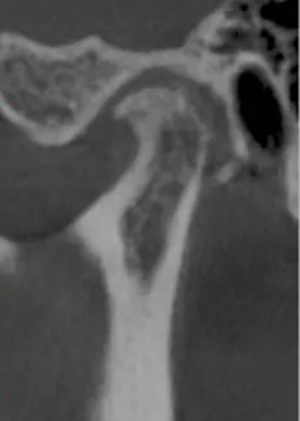

更嚴重的是會影響下頜關節(jié)的健康,正常下頜運動三模式開口運動,側方咬合,前伸下頜,閉鎖合時只留開口運動模式了,其他二種只有先開口后才能發(fā)生。這樣由于上前牙內傾,強迫下頜后退,使下頜關節(jié)位置異常,關節(jié)頭越磨越平。這類人群往往有關節(jié)區(qū)疼痛、張閉口彈響,張不開口等,嚴重的會影響日常生活和情緒。

關節(jié)頭損傷